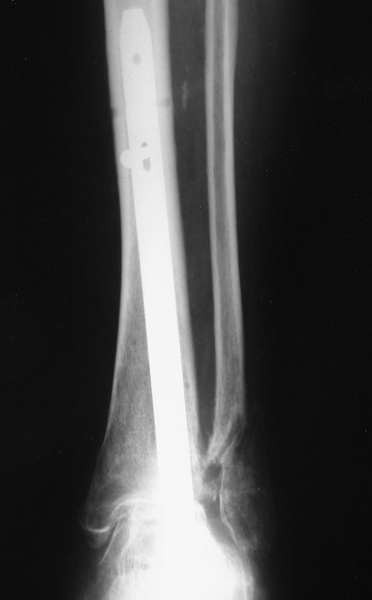

Мы бы сделали тоже самое с остатками лодыжек, но артродез, который безусловно показан, выполнили бы закрыто блокируемым штифтом (типа DFN) через пятку. Опороспособность восстановится сразу, артродез (рентгенологический) наступит месяцев через 4-6.

С уважением, А.Семенистый.

Можно: 65-летняя пациентка, оперирована по поводу несросшегося в гипсе перелома лодыжек с патологической вальгусной установкой стопы и выраженным нарушением опрной функции. Оперирована через 6 месяцев после травмы. Рентгенограммы через 4 месяца после операции.